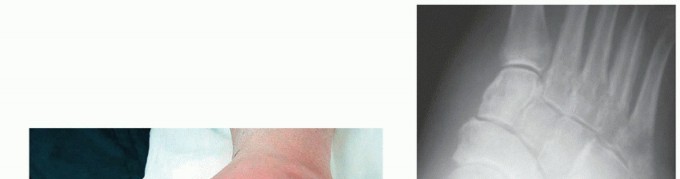

The two most common methods of internal fixation currently employed are large beaming intramedullary screws or rigid medial plate and screw constructs (FIG 7).22,25

--- FIG 7 • A,B. Preoperative weight-bearing radiographs on a 57-year-old diabetic female with no open wounds. She underwent correction of the deformity followed by internal fixation with super construct beaming screws.

FIG 7 • (continued) C,D. Radiographs at 1 year, demonstrating successful union.*